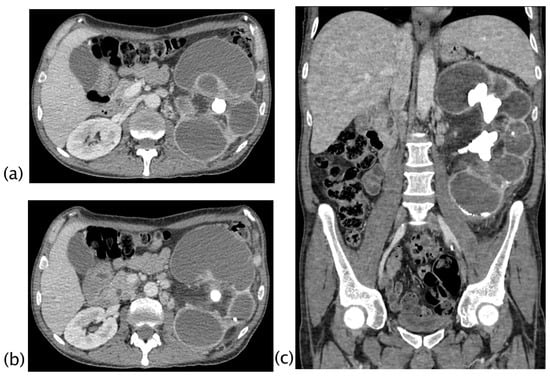

Figure 5.

Xanthogranulomatous pyelonephritis Stage III—pararenal form CT with contrast agent: axial (a,b), coronal (c), and sagittal (d) MPR reconstruction. In the right kidney, staghorn lithiasis is present; gross vesical lithiasis is also visible. The walls of the ureter are thickened and hyperemic. The CT was performed after nephrostomy placement, so significant calico-pyelic dilatation is not significant. Peri- and pararenal collections are evident, particularly the inferior polar collection (c) that passes the perirenal fascia. Posteriorly (b), the inflammatory process passes and infiltrates the psoas muscle. The staghorn lithiasis, the coexistence of calico-pyelic dilatation and fluid collections, and especially, the high invasiveness of the pathology, allowed, with high diagnostic confidence, to make the diagnosis of XGP.